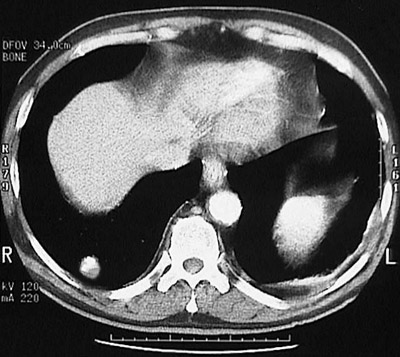

| This chest CT scan a "soft tissue window" density reveals a small rounded mass with bright calcification near the base of the right lung. This is a pulmonary hamartoma. These uncommon benign tumors have cartilage, vessels, and epithelial elements. Some have calcifications as well. |